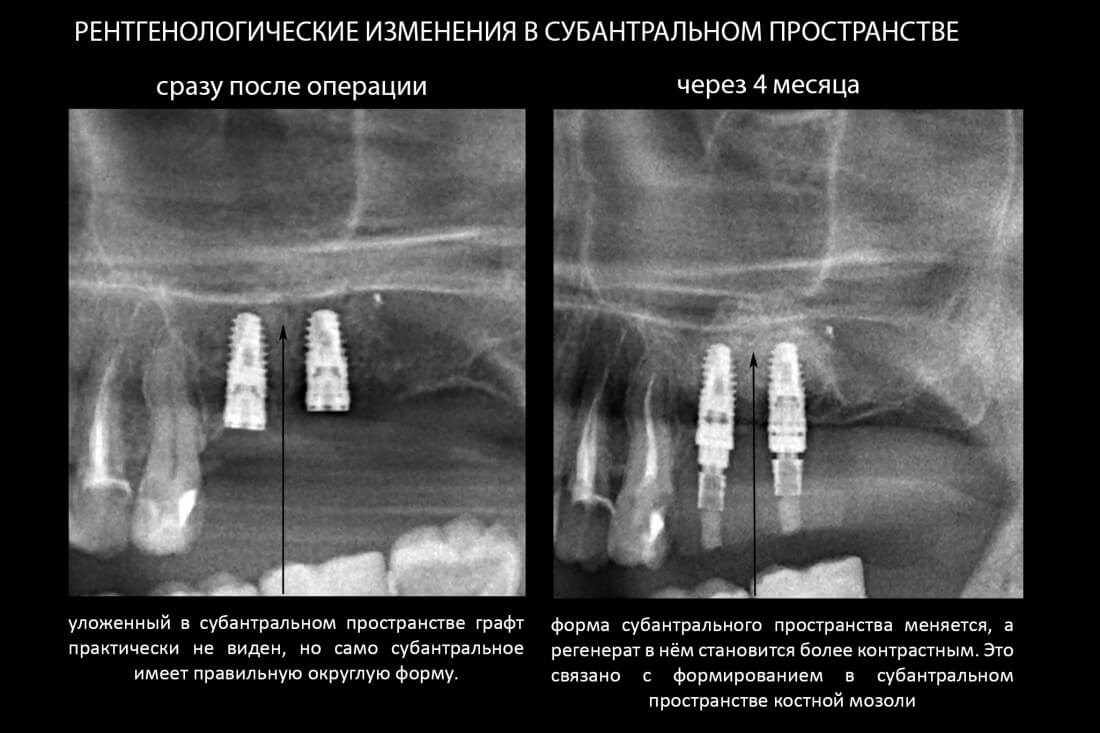

Простой синуслифтинг. Часть III.